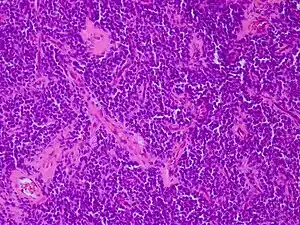

Micrograph of an H&E stained section of a peripheral PNET.

Peripheral PNET

The peripheral PNET (pPNET) is now thought to be virtually identical to Ewing sarcoma:

"Current evidence indicates that both Ewing's sarcoma and PNET have a similar neural phenotype and, because they share an identical chromosome translocation, they should be viewed as the same tumor, differing only in their degree of neural differentiation. Tumors that demonstrate neural differentiation by light microscopy, immunohistochemistry, or electron microscopy have been traditionally labeled PNETs, and those that are undifferentiated by these analyses have been diagnosed as Ewing's sarcoma."[6]